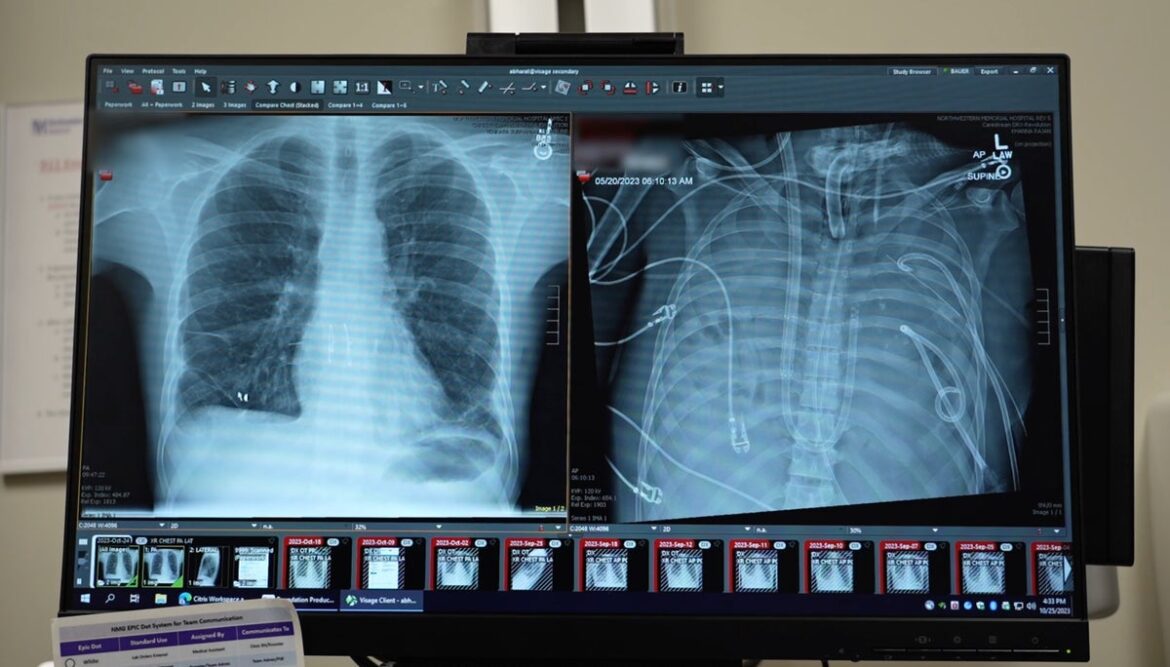

New lungs (left) that were transplanted into a patient after he was kept alive with artificial lungs are seen next to his old lungs (right).